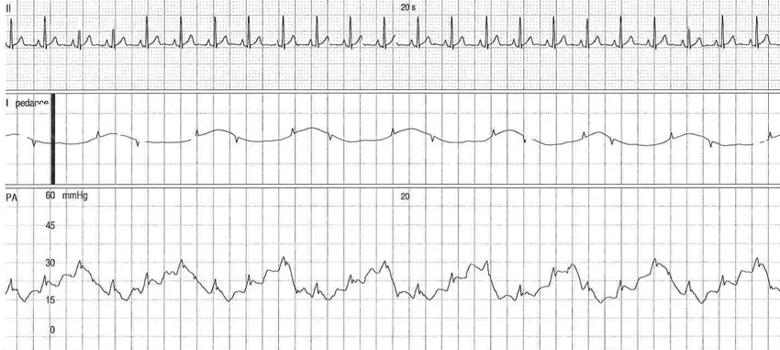

The patient underwent invasive cardiopulmonary exercise testing, given the persistent dyspnea with minimal activities. During the test we noted the presence of postcapillary PH with an end-expiratory PAWP of 26 mm Hg. We suspected a high intrathoracic pressure given obesity and pronounced respiratory oscillation with positional changes of his pulmonary pressures. Esophageal manometry revealed an end-expiration supine pressure of 18 mm Hg (Figure 1), hence the adjusted PAWP was normal at 8 mm Hg. In addition, the PAWP/cardiac output slope was normal (< 2 Wood units) during the exercise test and therefore not supportive of postcapillary PH with activities.

Figure 1. End-expiratory PAWP (A) and intrathoracic pressures (B) in supine position.